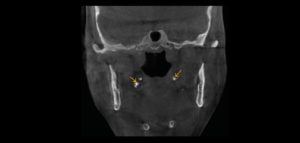

La reabsorción radicular interna (RRI) es una afección inflamatoria que resulta en la destrucción progresiva de la dentina intra-radicular a lo largo de los tercios